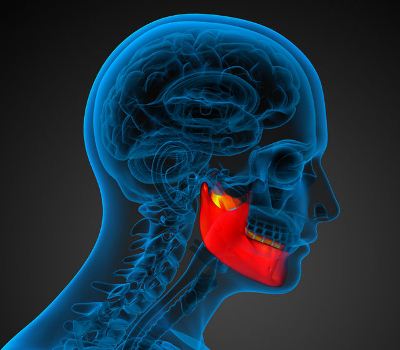

5 de abril de 2017

Revisión del cáncer oral

La doctora Aránzazu Fernández Larrañaga, Cirujano Oral y Maxilofacial del Hospital Quirónsalud Zaragoza, nos habla del cáncer oral, su incidencia, factores de riesgo y posibles tratamientos, así como de la importancia de la higiene y la alimentación saludable

Reconstrucción de la mandíbula tras la extirpación de un tumor

El defecto generado al reseccionar un tumor mandibular se puede subsanar durante la misma intervención mediante un autoimplante

En los casos de cáncer en los que las zonas afectadas son la cabeza o el cuello, al problema sin duda principal del propio tumor, se añaden otros secundarios como la estética, las complicaciones para comer o hablar, etc. Por esta razón, cua...